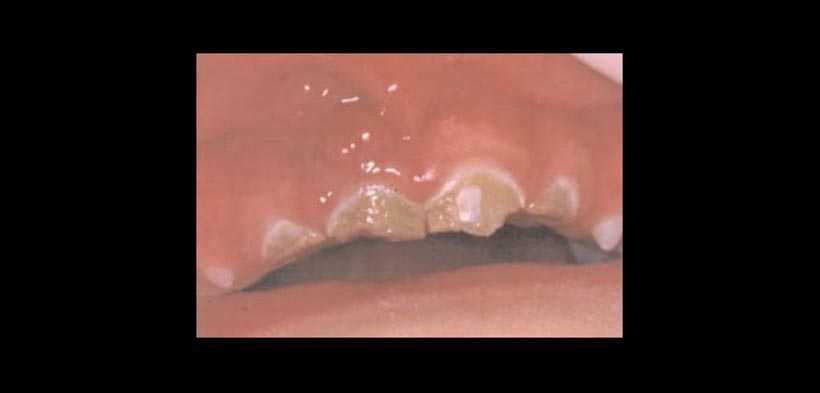

Fig. 1. Caries de infancia temprana: A) Estadio moderado: alteración temprana de las superficies lisas vestibulares de los dientes antero- superiores, manteniéndose sanos los inferiores. B) aspecto de la superficie palatina.

Fig. 2. Caries de infancia temprana: estadio avanzado.